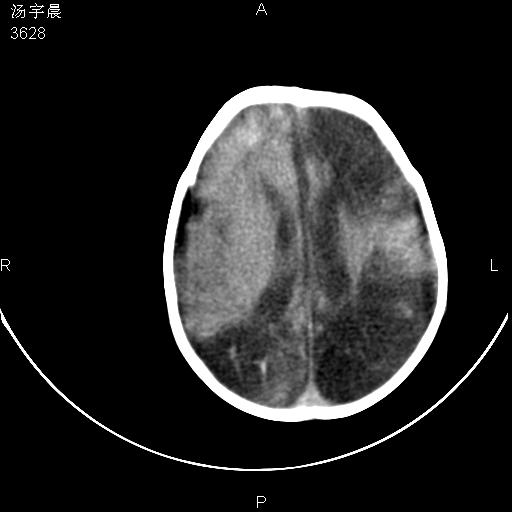

早产儿,现两月大,2月份在某医院诊断病毒性脑炎并治疗,mri报右颞部脑白质片状长t2信号,脑白质模糊。其他不详,现家属要求ct复查 。

双侧大脑半球大片状低密度,无明显占位表现, 符合病毒性脑炎。

小儿病毒性脑炎ct表现缺乏特异性,但其定位分布有一定特异性,单纯疱疹病毒性脑炎ct表现以颢叶病变为主,同时可累及其他脑区或伴出血,乙型脑炎表现为基底及丘脑的病变,流行性腮腺病毒性脑炎则ct表现可正常,故ct检查对病毒性脑炎的定性有重要的价值。 本例支持:病毒性脑炎的后遗改变!